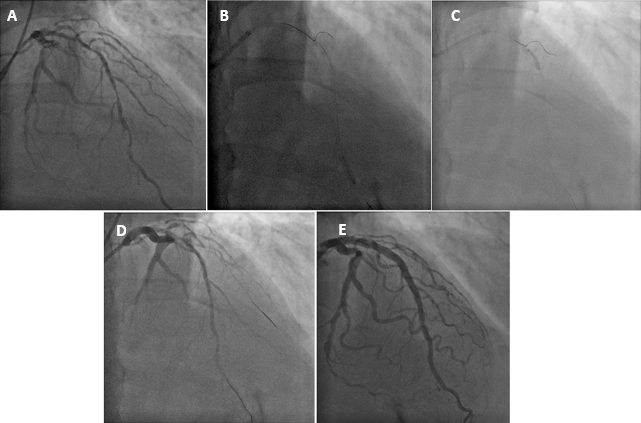

A 65-year-old man was admitted with non-ST-segment elevation myocardial infarction (NSTEMI). Coronary angiography showed a left dominant system with severe and diffuse left anterior descending artery (LAD) disease (Figure 1A, Video 1), necessitating percutaneous coronary intervention (PCI). LAD wiring was uneventful. Wiring of the diagonal artery for protection was difficult due to its retroflex take-off from the LAD and severe downstream disease. A Sion Black (Asahi Intecc) wire was able to select the diagonal branch but failed to negotiate across the more distal lesion despite support of a Finecross (Terumo) microcatheter (Figure 1B). Advancement of a small 1.0 mm x 5 mm compliant balloon led to wire prolapse into the LAD. With the inflation of a 3.0 mm x 15 mm non-compliant (NC) balloon in LAD (Figure 1C), the Sion Black wire was able to negotiate across the diagonal lesions (Figure 1D, Video 2). This was followed by successful stenting of the LAD, resulting in excellent final angiographic results with good side branch patency (Figure 1E, Video 3).